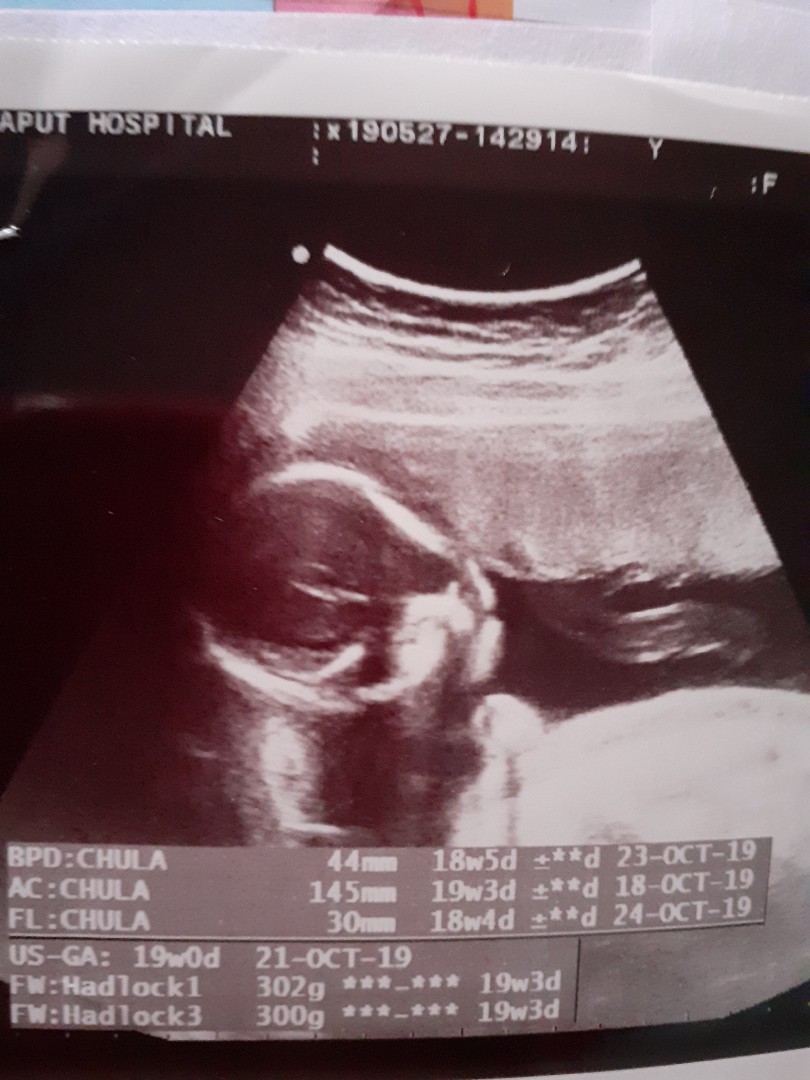

บ้านนี้17Wน้องผู่หญิงค่ะ